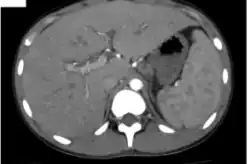

| Severe hepatosplenomegaly | |

Hepatosplenomegaly (commonly abbreviated HSM) is the simultaneous enlargement of both the liver (hepatomegaly) and the spleen (splenomegaly). Hepatosplenomegaly can occur as the result of acute viral hepatitis, infectious mononucleosis, and histoplasmosis or it can be the sign of a serious and life-threatening lysosomal storage disease. Systemic venous hypertension can also increase the risk for developing hepatosplenomegaly, which may be seen in those patients with right-sided heart failure.